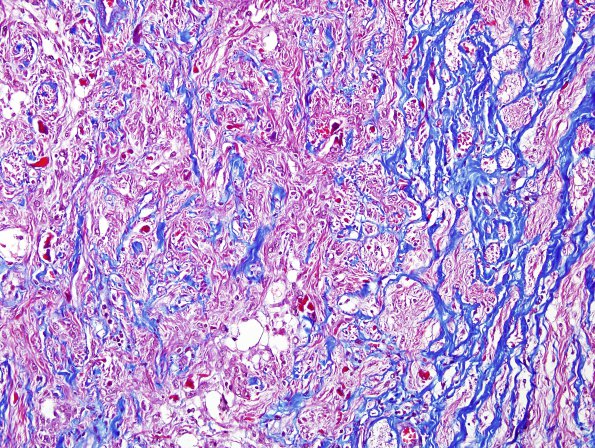

The portion of the intraneural and intradural sleeve are separated and invaded as shown in this trichrome stain for collagen.